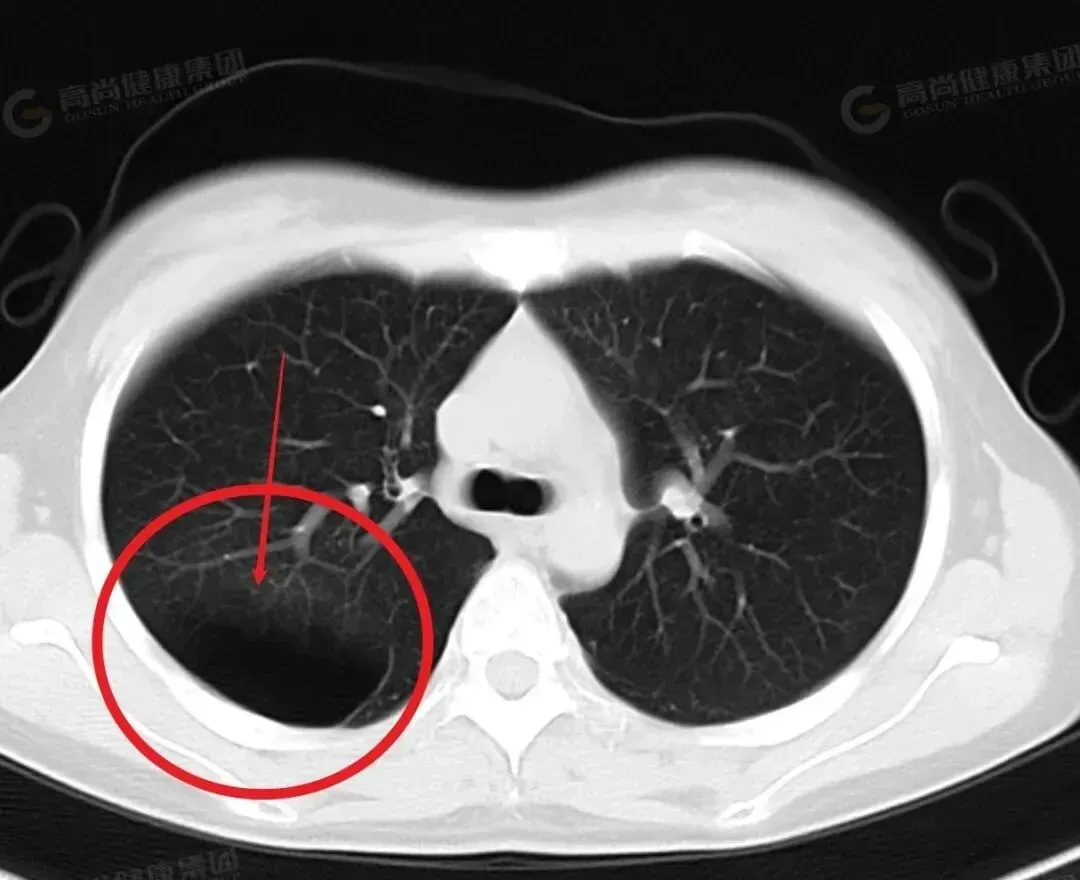

标准二:影像检查显示肿瘤缩小或消失,没有新病灶

CT、核磁共振(MRI)一看,原来的肿瘤肿块明显缩小了,比如从3厘米缩到1厘米,甚至完全看不见了,全身也没发现新的病灶。这是病情好转最硬核的证据,也是医生判断疗效的核心。只要出现这种情况,那就是实打实的在往好处走。